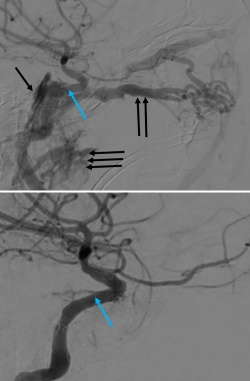

Direct CCFs are unlikely to close spontaneously, and upfront treatment is indicated due to the risk of neurological deficits and worsening of venous congestion. Signs for urgent treatment of direct CCFs include visual impairment, progressive paresis of extraocular muscles, intractable orbital pain, bruit, and progressive exophthalmos.[14][18] Because direct CCFs originate from a defect in the cavernous ICA either from an aneurysm rupture or dissection, the goal of treatment is to cease flow into the CS and reconstruct the cavernous ICA. There are numerous endovascular techniques utilized to achieve this end including coil embolization (Figure 5), coil embolization with balloon remodeling of the ICA and coil embolization with stent-assistance.[35][36][37] Combined transvenous and transarterial approaches can be used to preserve the ICA and pack the CS with coils to stop flow. Liquid embolics such as Onyx (ethylene vinyl alcohol copolymer, Medtronic, USA) and n-butyl cyanoacrylate glue (n-BCA, Trufill, Cerenovus, USA) are less commonly used for direct CCF due to the risk of distal embolization into cerebral arteries and stroke. A large cavernous ICA defect such as that from a traumatic transection may require ICA sacrifice as a life-sustaining treatment. Parent vessel sacrifice (endovascular occlusion) may also be option in cases of recurrence if the patient passes a balloon test occlusion. Less commonly used approaches include covered stents, packing the cavernous sinus via open microsurgery, and cavernous ICA trapping with bypass.

Endovascular treatment of indirect CCFs is primarily via a transvenous route unlike treatment of direct CCF.[35][39] Transarterial embolization is often primarily attempted via the femoral artery. Occasionally fistulous connection from dural branches the ICA limits the transarterial approach due to the risk of stroke and arterial dissection with treatment. When anatomic variations limit transarterial access, transvenous embolization may be attempted via the petrosal sinuses and pterygoid plexus. Additionally, an orbital surgeon may be asked to expose the superior ophthalmic vein via an anterior orbitotomy for direct canulation.[40][41] Embolization proceeds with detachable coils or liquid embolics (Onyx, n-BCA) to obliterate the fistula, restore normal orbital venous drainage and preserve intradural arterial flow. During transvenous embolization, the arterial circulation is monitored with intermittent angiography via the ipsilateral ICA to ensure the patency of normal cerebral vasculature.